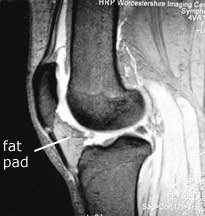

Note the relationship of the fat pad to the patellar tendon, and hence the extensor mechanism. It fills the space from the patellar tendon all of the way to the cruciate ligaments. In fact, it also extends sideways, making the bulge that one can often see in a normal knee on either side of the patella (red arrow). Normally the fat pad is not attached to either the meniscus or the patella, and is separated from the patellar tendon by the deep infrapatellar bursa.

With arthrofibrosis fat pad the fat pad becomes thickened and fibrosed, and the deep infrapatellar bursa can be obliterated. The fat pad can become adherent to the anterior horn of the meniscus and to the patella, and via the obliteration of the deep infrapatellar bursa it becomes adherent to the patellar tendon also. This thickened fat pad may also become tethered to the intercondylar notch where the cruciate lies.

Note also from the MRI that the fat pad is truly in contact with the bony lower edge of the patella. If that fat pad is scarred and contracted, can you imagine how it can pull the patella downward?

The cruciate ligaments, by their complex position of the knee, anchor the femur to the tibia. Superimpose in your mind’s eye the photograph above upon this illustration of the intercondylar notch and the cruciate ligaments. Imagine how the fat pad tucks into the femoral notch, and how easily it and the cruciates can both be involved in the arthrofibrotic scarring process.